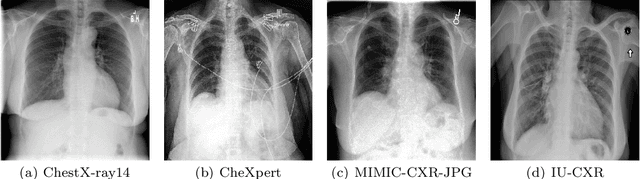

Medical imaging has been used for diagnosis of various conditions, making it one of the most powerful resources for effective patient care. Due to widespread availability, low cost, and low radiation, chest X-ray is one of the most sought after radiology examination for the diagnosis of various thoracic diseases. Due to advancements in medical imaging technologies and increasing patient load, current radiology workflow faces various challenges including increasing backlogs, working long hours, and increase in diagnostic errors. An automated computer-aided diagnosis system that can interpret chest X-rays to augment radiologists by providing actionable insights has potential to provide second opinion to radiologists, highlight relevant regions in the image, in turn expediting clinical workflow, reducing diagnostic errors, and improving patient care. In this study, we applied a novel architecture augmenting the DenseNet121 Convolutional Neural Network (CNN) with multi-head self-attention mechanism using transformer, namely SA-DenseNet121, that can identify multiple thoracic diseases in chest X-rays. We conducted experiments on four of the largest chest X-ray datasets, namely, ChestX-ray14, CheXpert, MIMIC-CXR-JPG, and IU-CXR. Experimental results in terms of area under the receiver operating characteristics (AUC-ROC) shows that augmenting CNN with self-attention has potential in diagnosing different thoracic diseases from chest X-rays. The proposed methodology has the potential to support the reading workflow, improve efficiency, and reduce diagnostic errors.